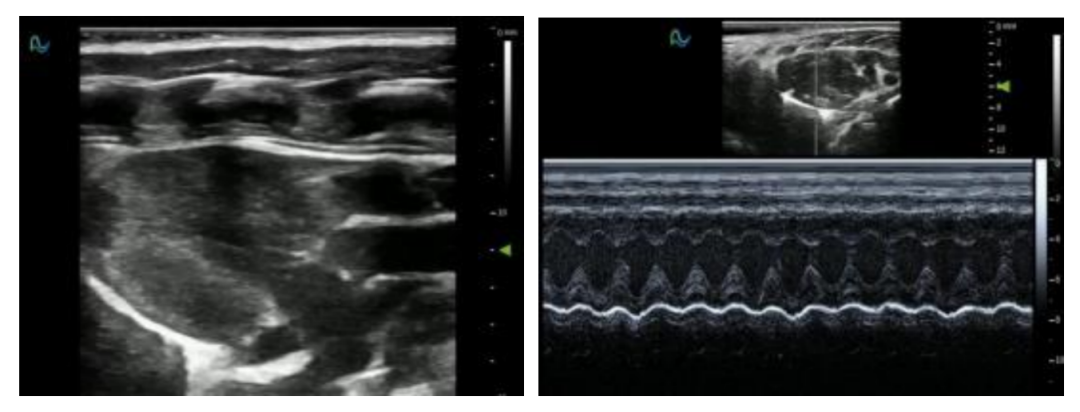

B超成像:基础解剖结构可视化;

M超成像:以时间为横轴,显示心脏等结构运动轨迹;

彩色/能量多普勒:血流方向与速度映射(血管通畅性评估);

脉冲/组织多普勒:精准测量血流速度与组织运动状态

心肌应变成像:定量分析心肌形变,检测早期心功能异常;

利用超声追踪心肌在心脏收缩和舒张过程中的运动,计算出不同方向的应变值(纵向、纵向和周向)。